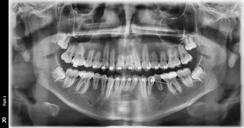

Figura 7. Lefort I. Figura 8. Osteotomía sagital. Figura 9. Mentoplastía. Figura 10. Cefálica de progreso. Figura 11. Panorámica de inicio.

Segunda fase quirúrgica de impactación maxilar Lefort I, 4 mm, (Figura 7), se realizó la cirugía mandibular que consistió en la osteotomía sagital de la rama bilateral de avance, 9 mm (Figura 8), se hizo la cirugía del mentón con la mentoplastía de avance 4 mm, (Figura 9) y una fase postquirúrgica de detallado y retención.

Estudios de progreso

Fueron realizados después de 1 año y 2 meses de haber iniciado el tratamiento y después de la cirugía. En los estudios radiológicos tenemos que en la radiografía lateral de cráneo las placas utilizadas para consolidar la fijación de los maxilares, la corrección de las relaciones esqueléticas en la Figura 10. En la panorámica inicial se señalan los gérmenes de los terceros molares (Figura 11) y en la Figura 12, la realización de las exodoncias de órganos dentarios 18, 28, 38 y 48.